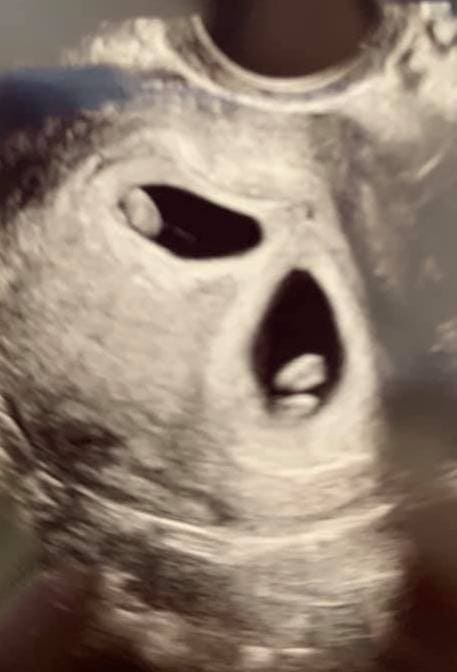

Early Twin Ultrasound at 7 Weeks

The earliest your doctor would likely order an ultrasound confirming twins would be 4 weeks pregnant. But unless you are going through fertility treatments, doing an ultrasound before 6 weeks isn’t very common, with the exception of complications. Women who are going through fertility treatments or have early complications may be able to have an early twin ultrasound at 4 or 5 weeks pregnant and find out they are pregnant with twins.

At four to five weeks after a pregnant woman’s last period the ultrasound commonly shows a small collection of fluid within the lining of the uterus that represents the early development of the gestational sac. At about five and a half weeks after a pregnant woman’s last period the ultrasound typically shows a gestational sac and within it we can see a 3-5 mm bubble-like structure, which is the yolk sac. At approximately six weeks after a pregnant woman’s last period, we can see a small fetal pole, one of the first stages of growth for an embryo, which develops alongside the yolk sac.